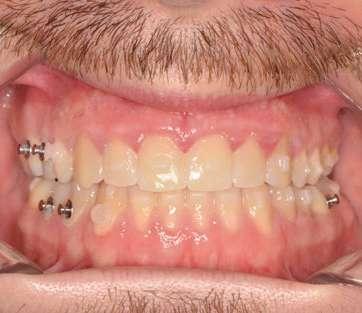

Fase 2: corrección con alineadores Una vez corregida la discrepancia transversal y finalizado el periodo de control, el tratamiento continuó con alineadores Spark™, con un protocolo de uso de 22 horas diarias y cambios de alineadores cada 10 días. El tratamiento con alineadores se planificó en 2 etapas. Una primera etapa para abordar el plano vertical y una etapa final para abordar el plano sagital.

Corrección vertical (Ilustración 7):

 Extrusión de incisivos superiores (1,7 mm) e inferiores (1,5 mm) con attachments de control radicular.

 Intrusión de molares mandibulares mediante turbo bites para facilitar el cierre de la mordida.

Como se puede apreciar en las imágenes adjuntas, la corrección vertical planificada se logró en su totalidad. En esta etapa, se colocaron carillas provisionales de composite de canino a canino en la arcada superior para mejorar la estética del paciente y compensar la discrepancia de Bolton (Ilustración 8). Para la corrección sagital se fabricó un nuevo juego de alineadores transparentes.

Corrección sagital (Ilustración 9):

 Corrección de la inclinación corono-distal de los premolares en el cuarto cuadrante mediante elásticos intermaxilares.

Ilustración 7. Fotografías iniciales, post-disyunción e intra-tratamiento tras el 1º set de alineadores Spark™ (corrección vertical).